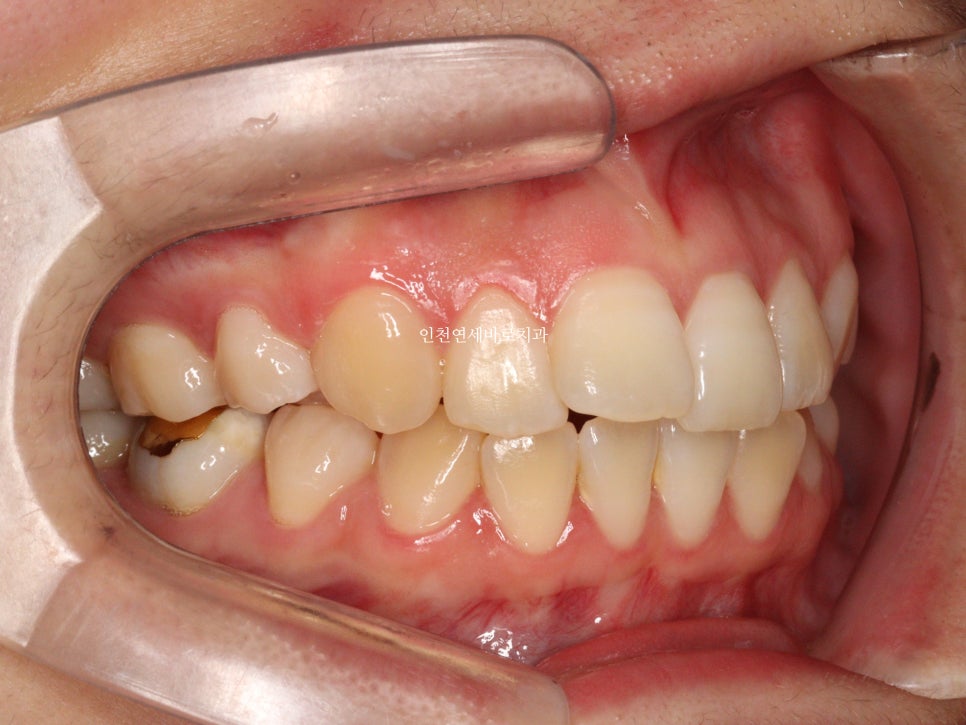

그리고 치료가 마무리 된 후의 모습입니다.

부분교정으로 앞니만 철사를 붙여서도 비슷한 효과를 볼 수 있었을지 모릅니다.

하지만 치아의 삭제가 많은 양 동반되지 않았다면 앞니가 분명 뻗쳐나왔을것입니다.

하지만 인비절라인은 전체교정에 준하는

치아와 주변조직에 무리가 되지 않는 범위에서의 확장을 만들어낼 수 있어

앞니의 뻗침을 최소화 할 수 있는 장점이 있습니다.

위 환자분의 재교정 치료기간은 약 7개월입니다.